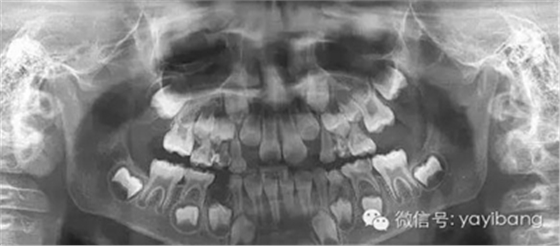

3、曲面斷層片 示恒牙萌出間隙不足